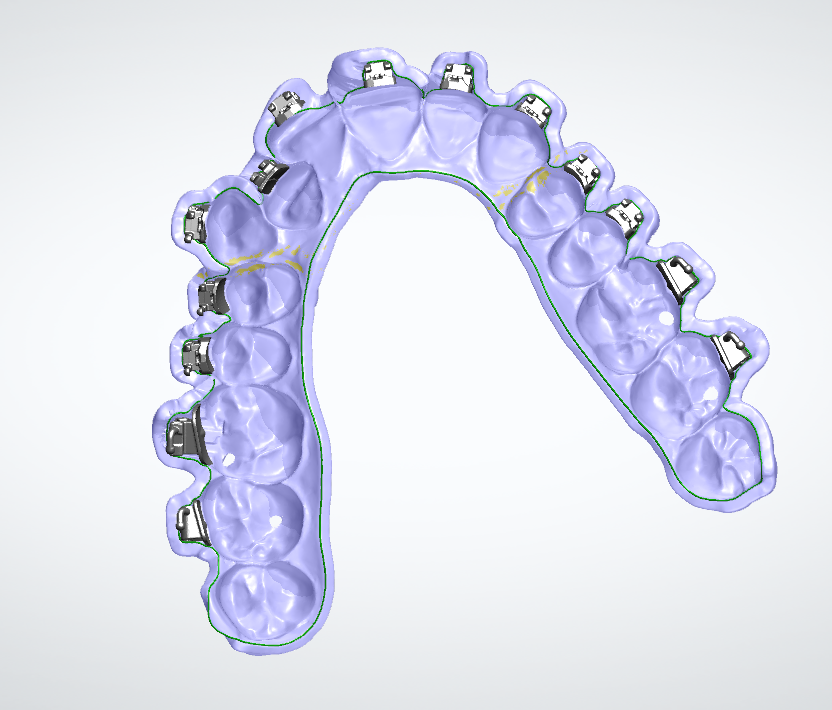

Полный расчет исходной ситуации в 3D цефалометрии. Составление плана лечения (ортосетап) в программе 3D Shape Ortodont.Загрузка КТ пациента-учет «движения корней» при лечении. Единственно правильный перенос положения брекетов или элайнеров - 3D печать полученного в программе результата (примеры представлены ниже на фото).

Наличие программного обеспечения позволяет использовать цифровые данные, полученные при диагностике в изготовлении протезов, шин, коронок без проблем «человеческого фактора», что очень важно при заболеваниях ВНЧС.